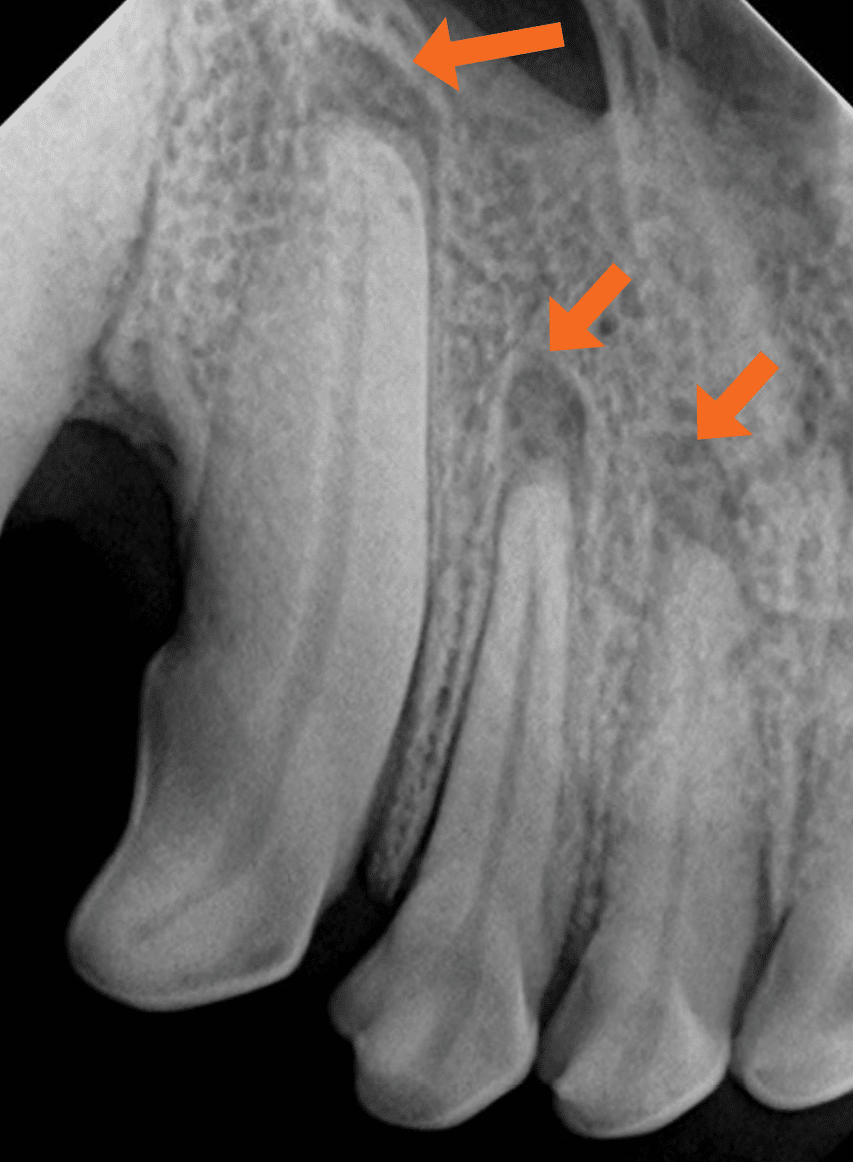

Dental X-rays are more than just tools for diagnosing cavities; they provide a comprehensive view of your oral health status. By allowing dentists to detect problems before they become severe, these images can save patients time, money, and discomfort in the long run. Early detection through modern imaging technology can reveal hidden decay between teeth, bone loss due to gum disease, or even cysts and tumors that are not visible during a standard exam.

Despite the myths surrounding dental x-rays, they play an integral role in preventative dentistry. X-rays allow dentists to detect issues that are not visible during a standard oral exam. This includes early signs of decay between teeth, problems below the gum line, and changes in bone density that could indicate periodontal disease. By identifying these problems early, fundamental dental treatments can be administered promptly, saving patients from more extensive and costly procedures down the line.